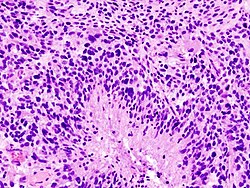

| Astrocytoma, IDH-mutant (CNS WHO grade 2 or grade 3) | glial processes (esp. on smear), nuclear atypia (typical size var. ~3x, irreg. nuc. membrane, hyperchromasia), no Rosenthal fibres in the core of the lesion †, no microvascular proliferation, no necrosis | often enhancing (suggests high grade), usu. supratentorial, usu. white matter | usu. old, occ. young | common | IDH-1(R132H)+/-, GFAP+ | File:Anaplastic astrocytoma - very high mag - cropped.jpg High-grade astrocytoma. (WC) |

| Glioblastoma, IDH-wildtype (CNS WHO grade 4) | glial processes (esp. on smear), nuclear atypia (typical size var. ~3x, irreg. nuc. membrane, hyperchromasia), no Rosenthal fibres in the core of the lesion †, microvascular proliferation or necrosis | often enhancing (suggests high grade), usu. supratentorial, usu. white matter | usu. old, occ. young | very common, esp. glioblastoma | IDH-1+/-, GFAP+ | File:Glioblastoma (1).jpg Glioblastoma. (WC) |